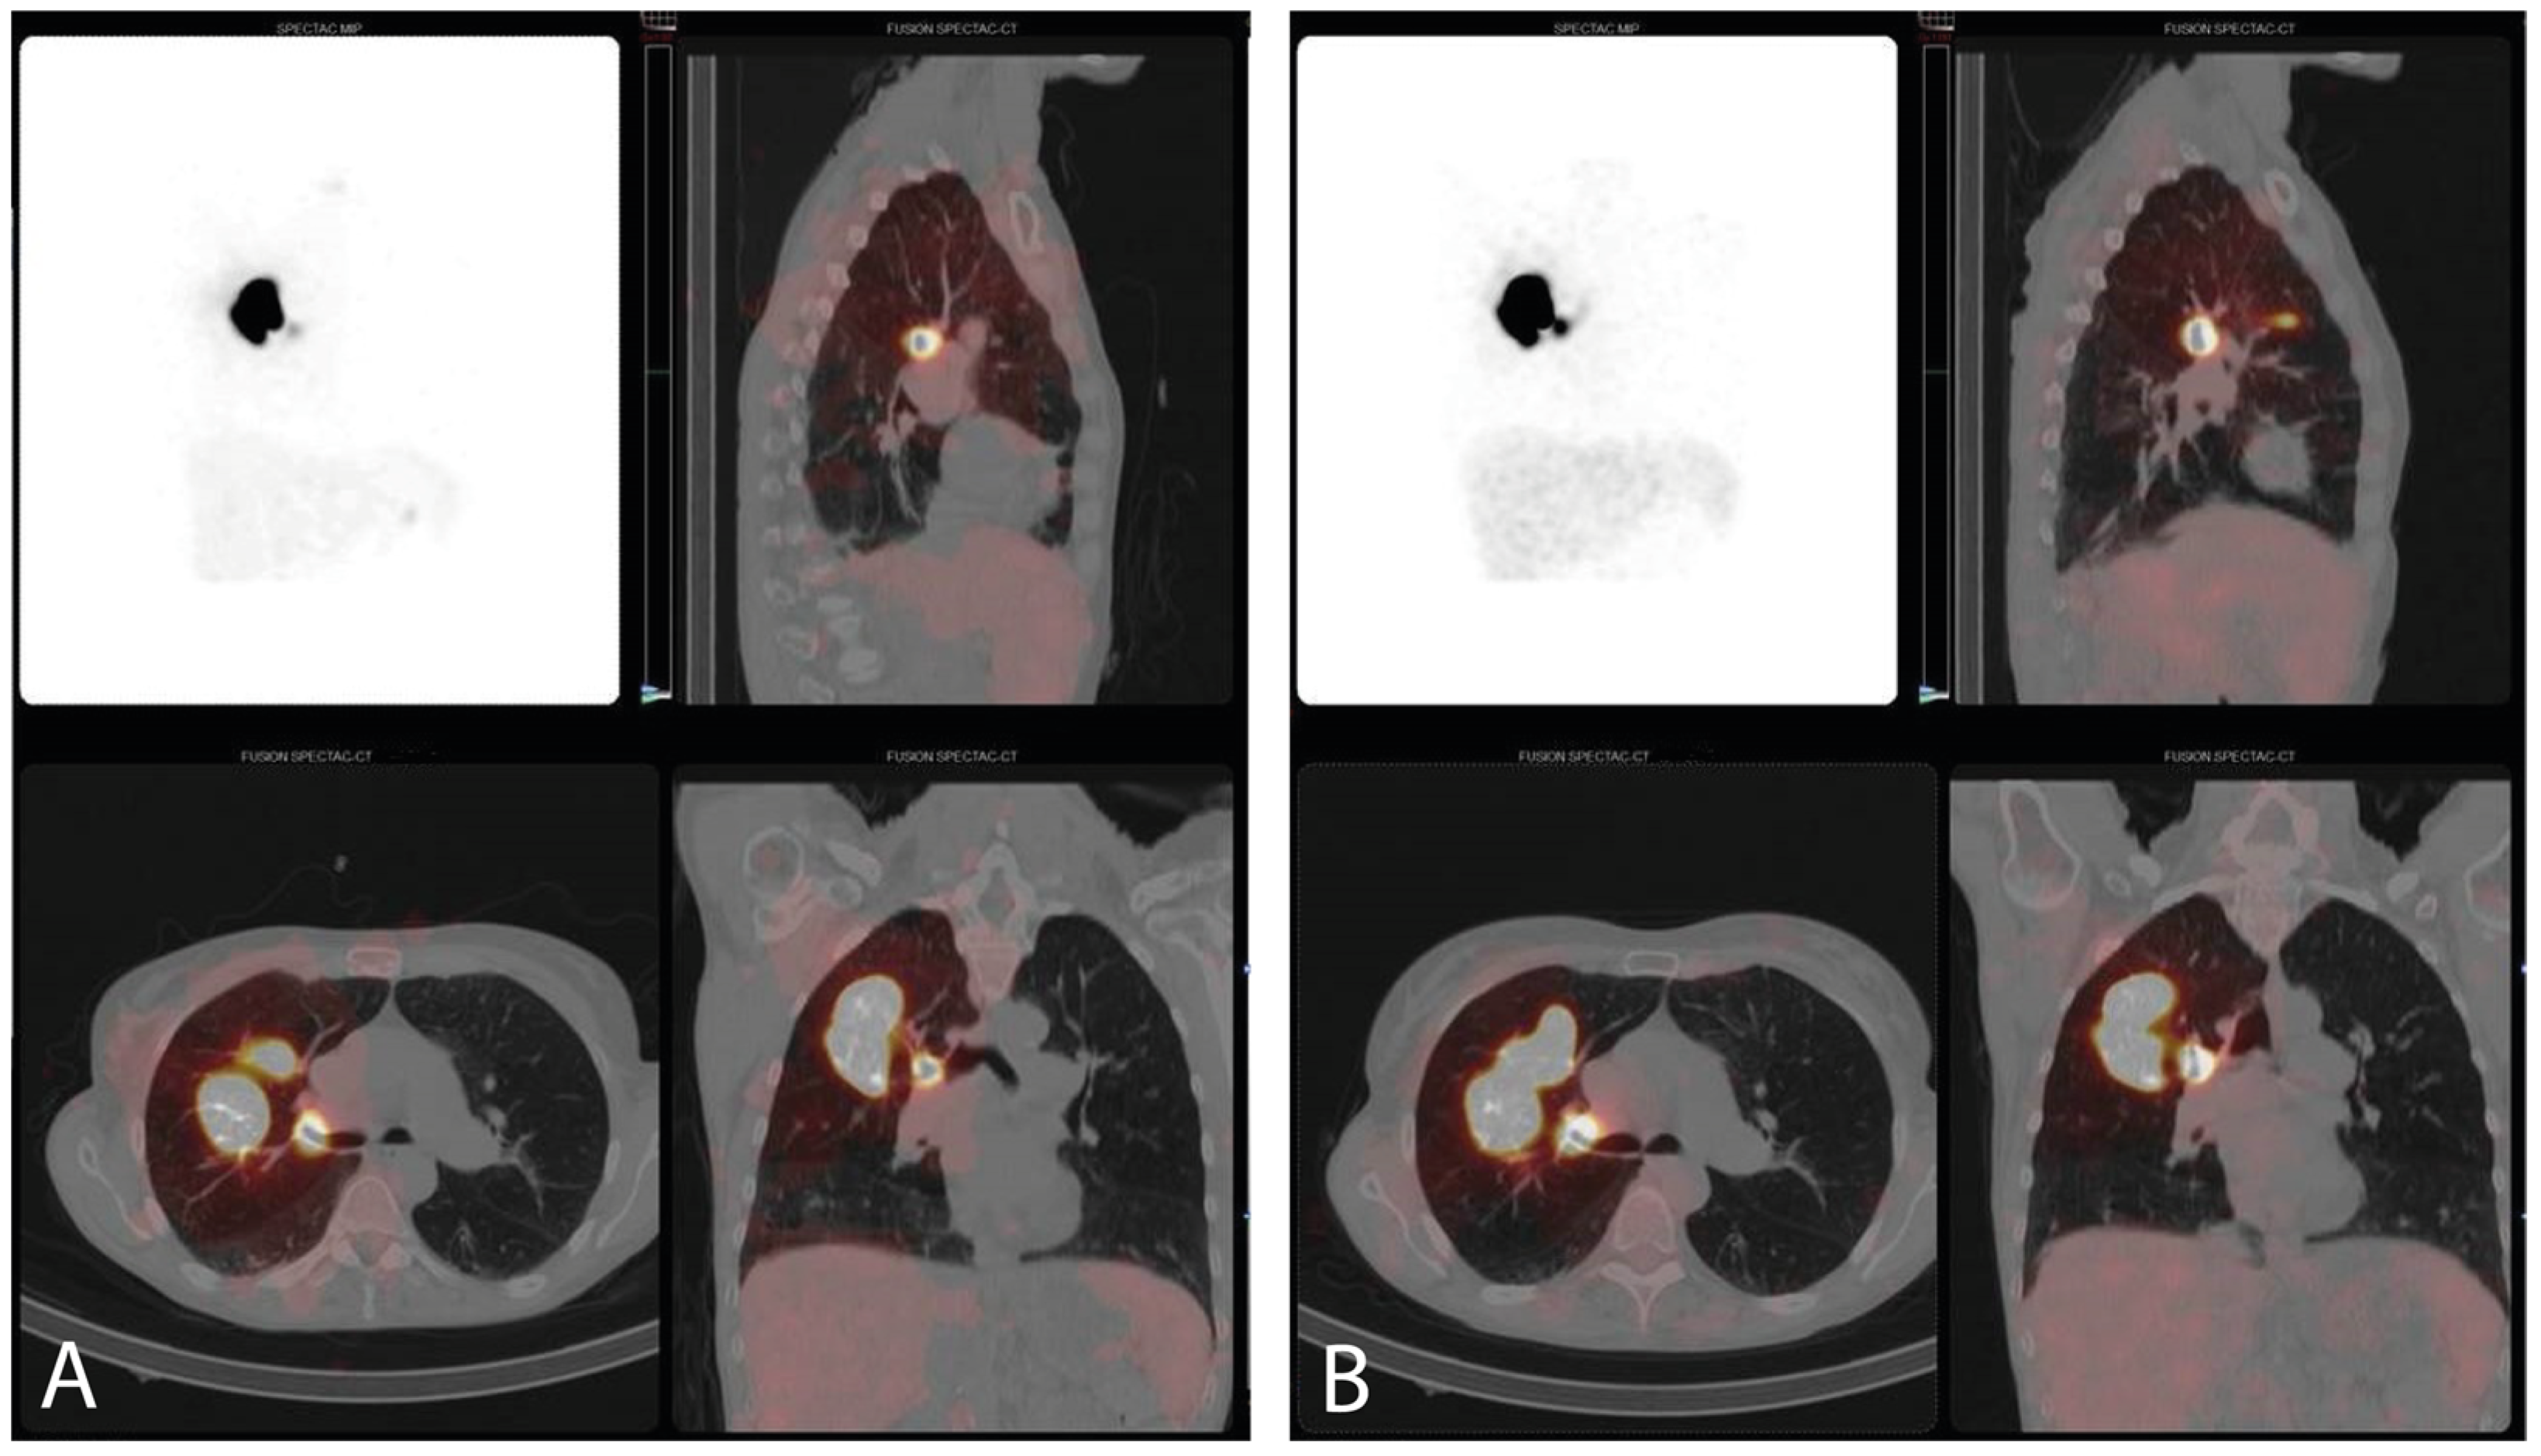

3.3. SPECT/CT Imaging and SLN Identification

| SLN identification, all scan times, n (%) | 10 (32.3%) | ||

| 5 (50.0%) | ||

| 9 (30.0%) | ||

| Endobronchial leakage, n (%) 6 | 9 (29.0%) | ||